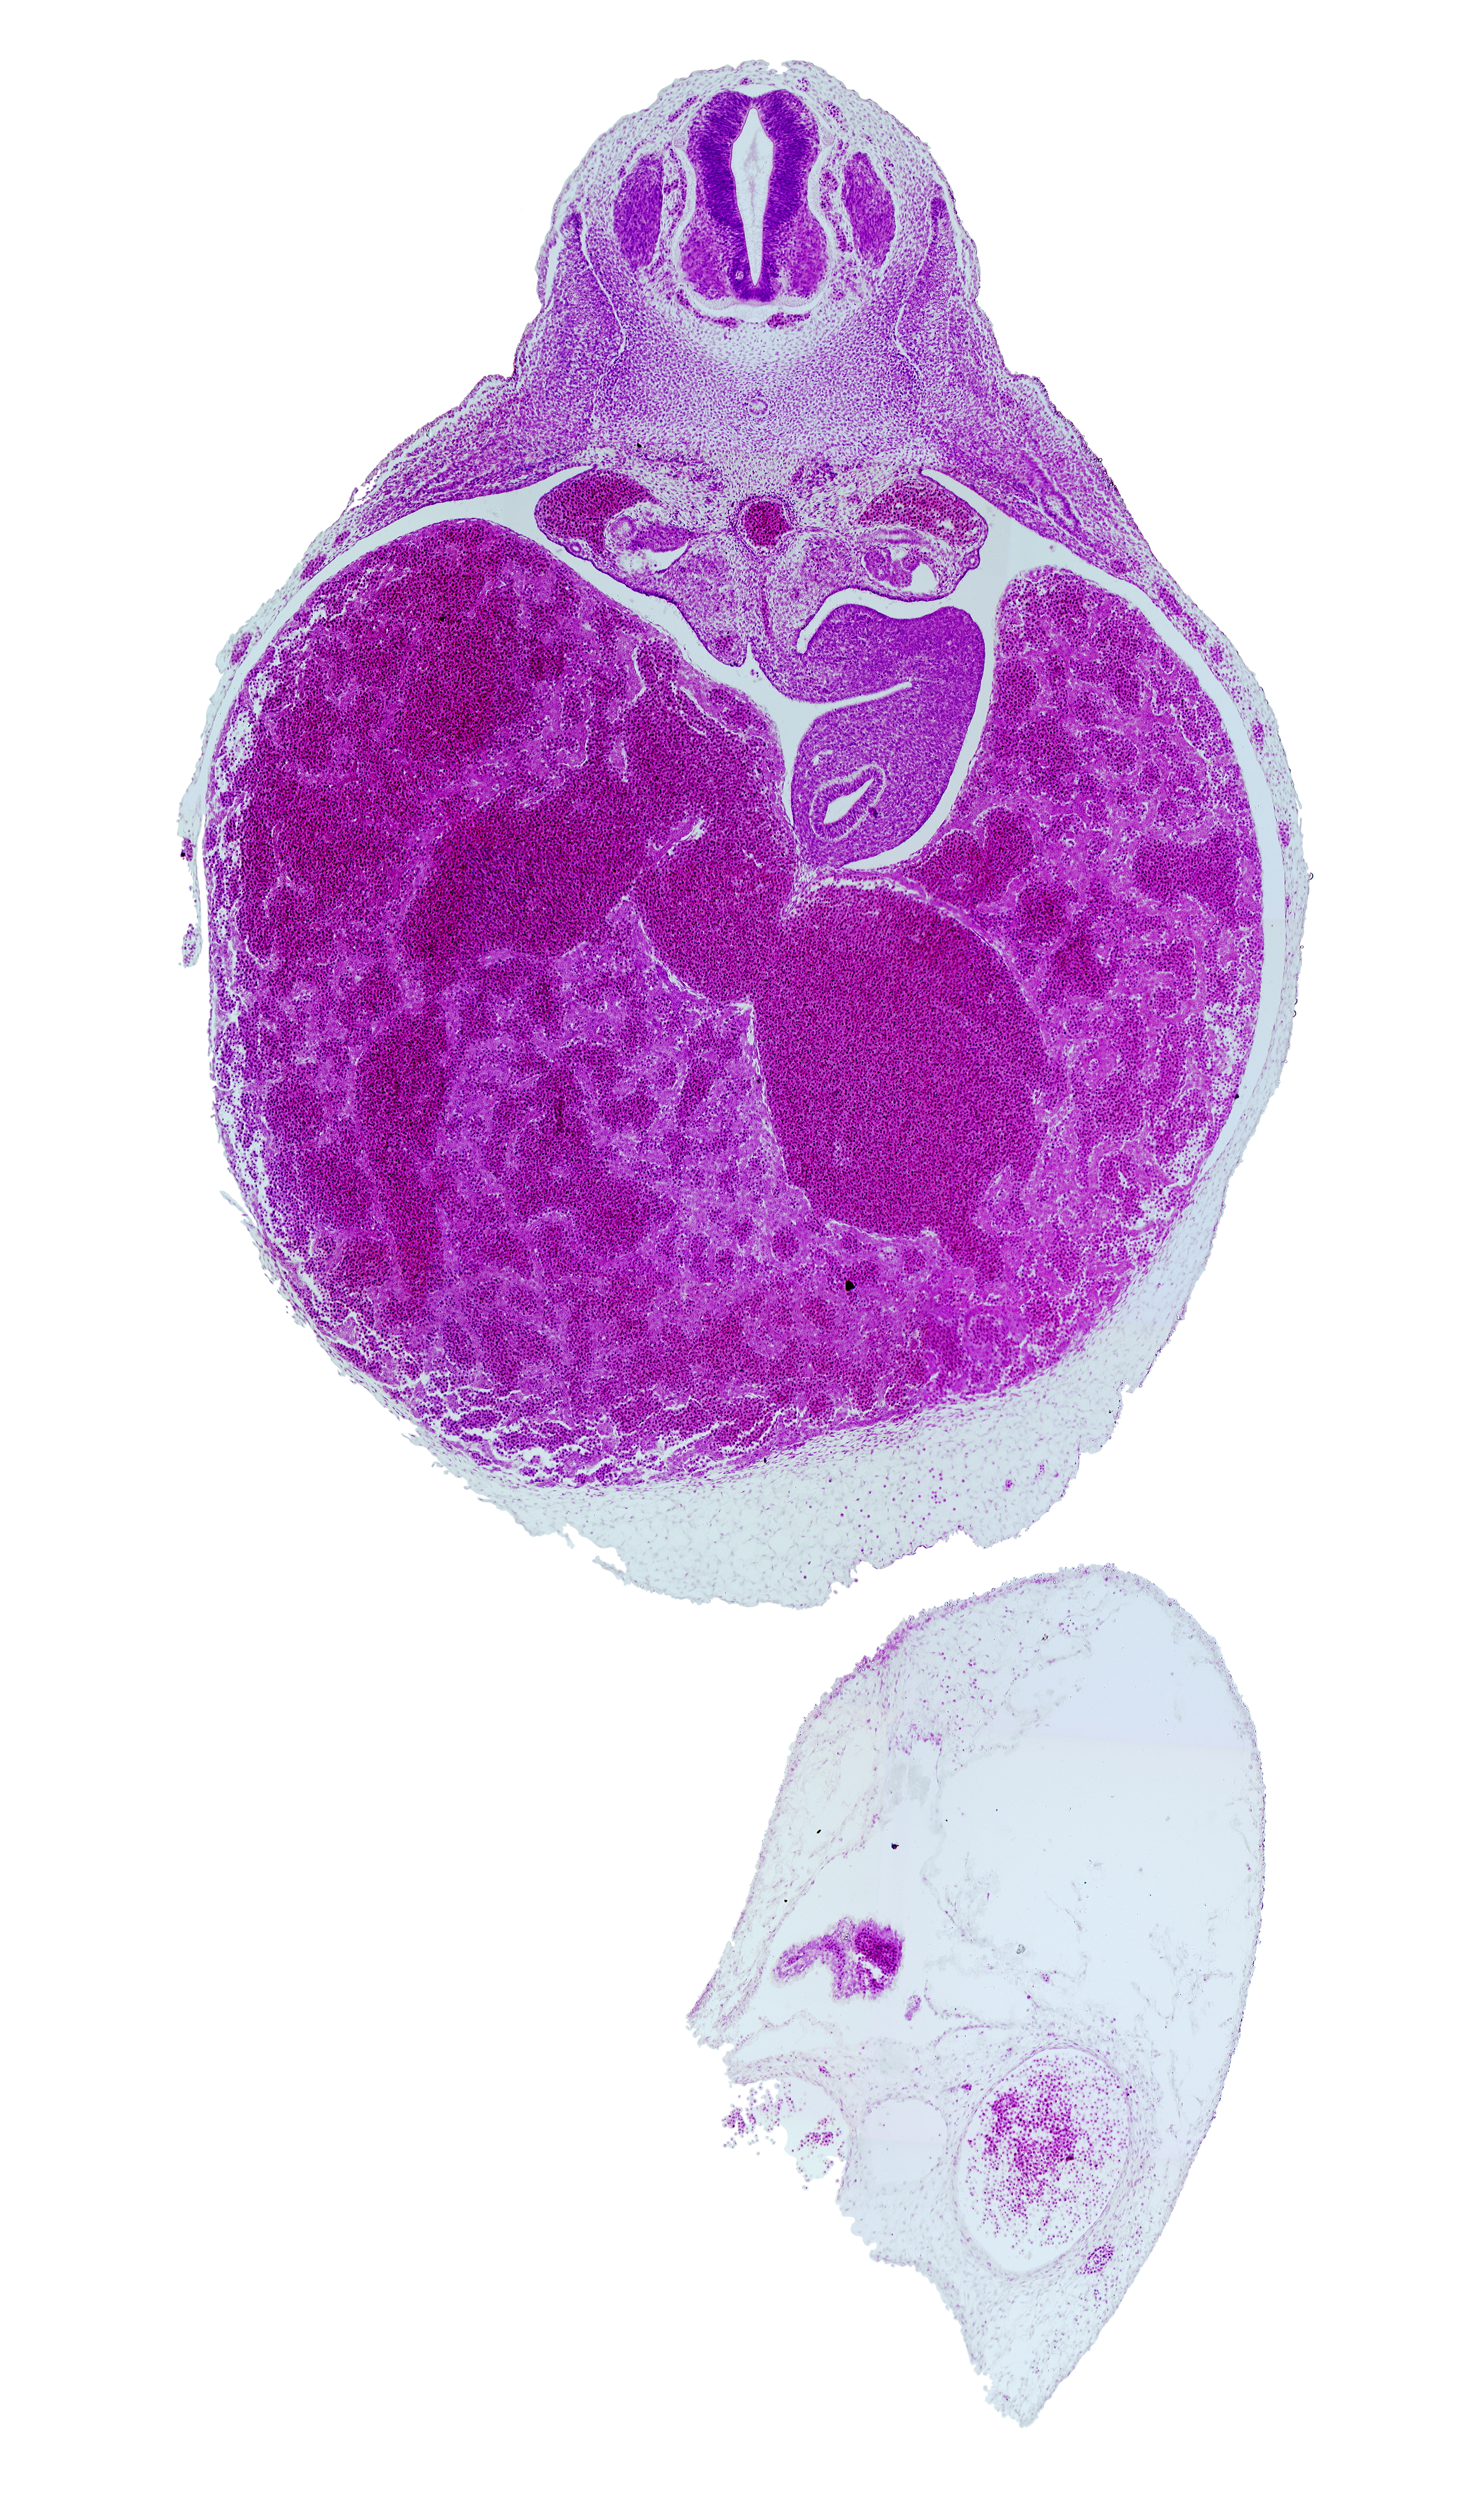

Carnegie Embryo #721 | Location: 16-03-01

Keywords: T-3 spinal ganglion, aorta, celiac artery, dorsal mesogastrium, ductus venosus, liver, neural arch blastema, postcardinal vein, stomach, suprarenal gland primordium, vertebral centrum blastema

Source: The Virtual Human Embryo.